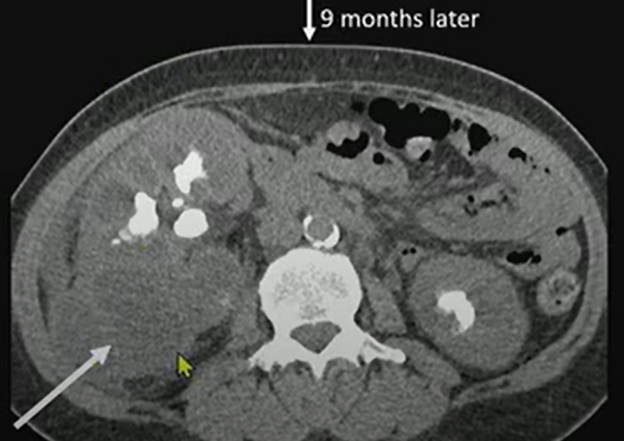

Nine months later, we see much more exuberant inflammation—soft-tissue thickening extending out from the kidney into the retroperitoneum.

- Extrarenal extension: Look for inflammation tracking into the retroperitoneum, psoas, or paraspinal muscles.

- Awareness of extrarenal spread is crucial to surgical planning.